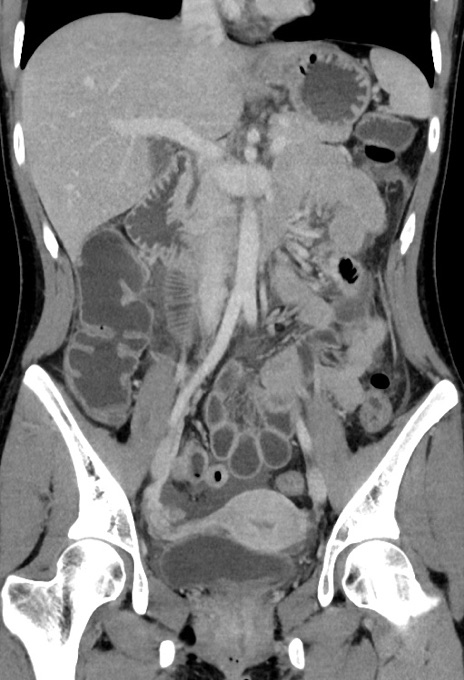

症例17(冠状断像)

【症例】20歳代女性

【主訴】嘔吐、下腹部痛

【現病歴】昨日夕食後に嘔吐し下腹部痛が出現。本日になっても嘔吐持続し改善しないため来院。

【身体所見】意識清明、BT 37.2℃、BP 108/67mmHg、腹部:平坦、やや硬、下腹部正中から右にかけて圧痛あり、反跳痛軽度あり、tapping pain(+)。

【データ】WBC 13600、CRP 14.94

横断像